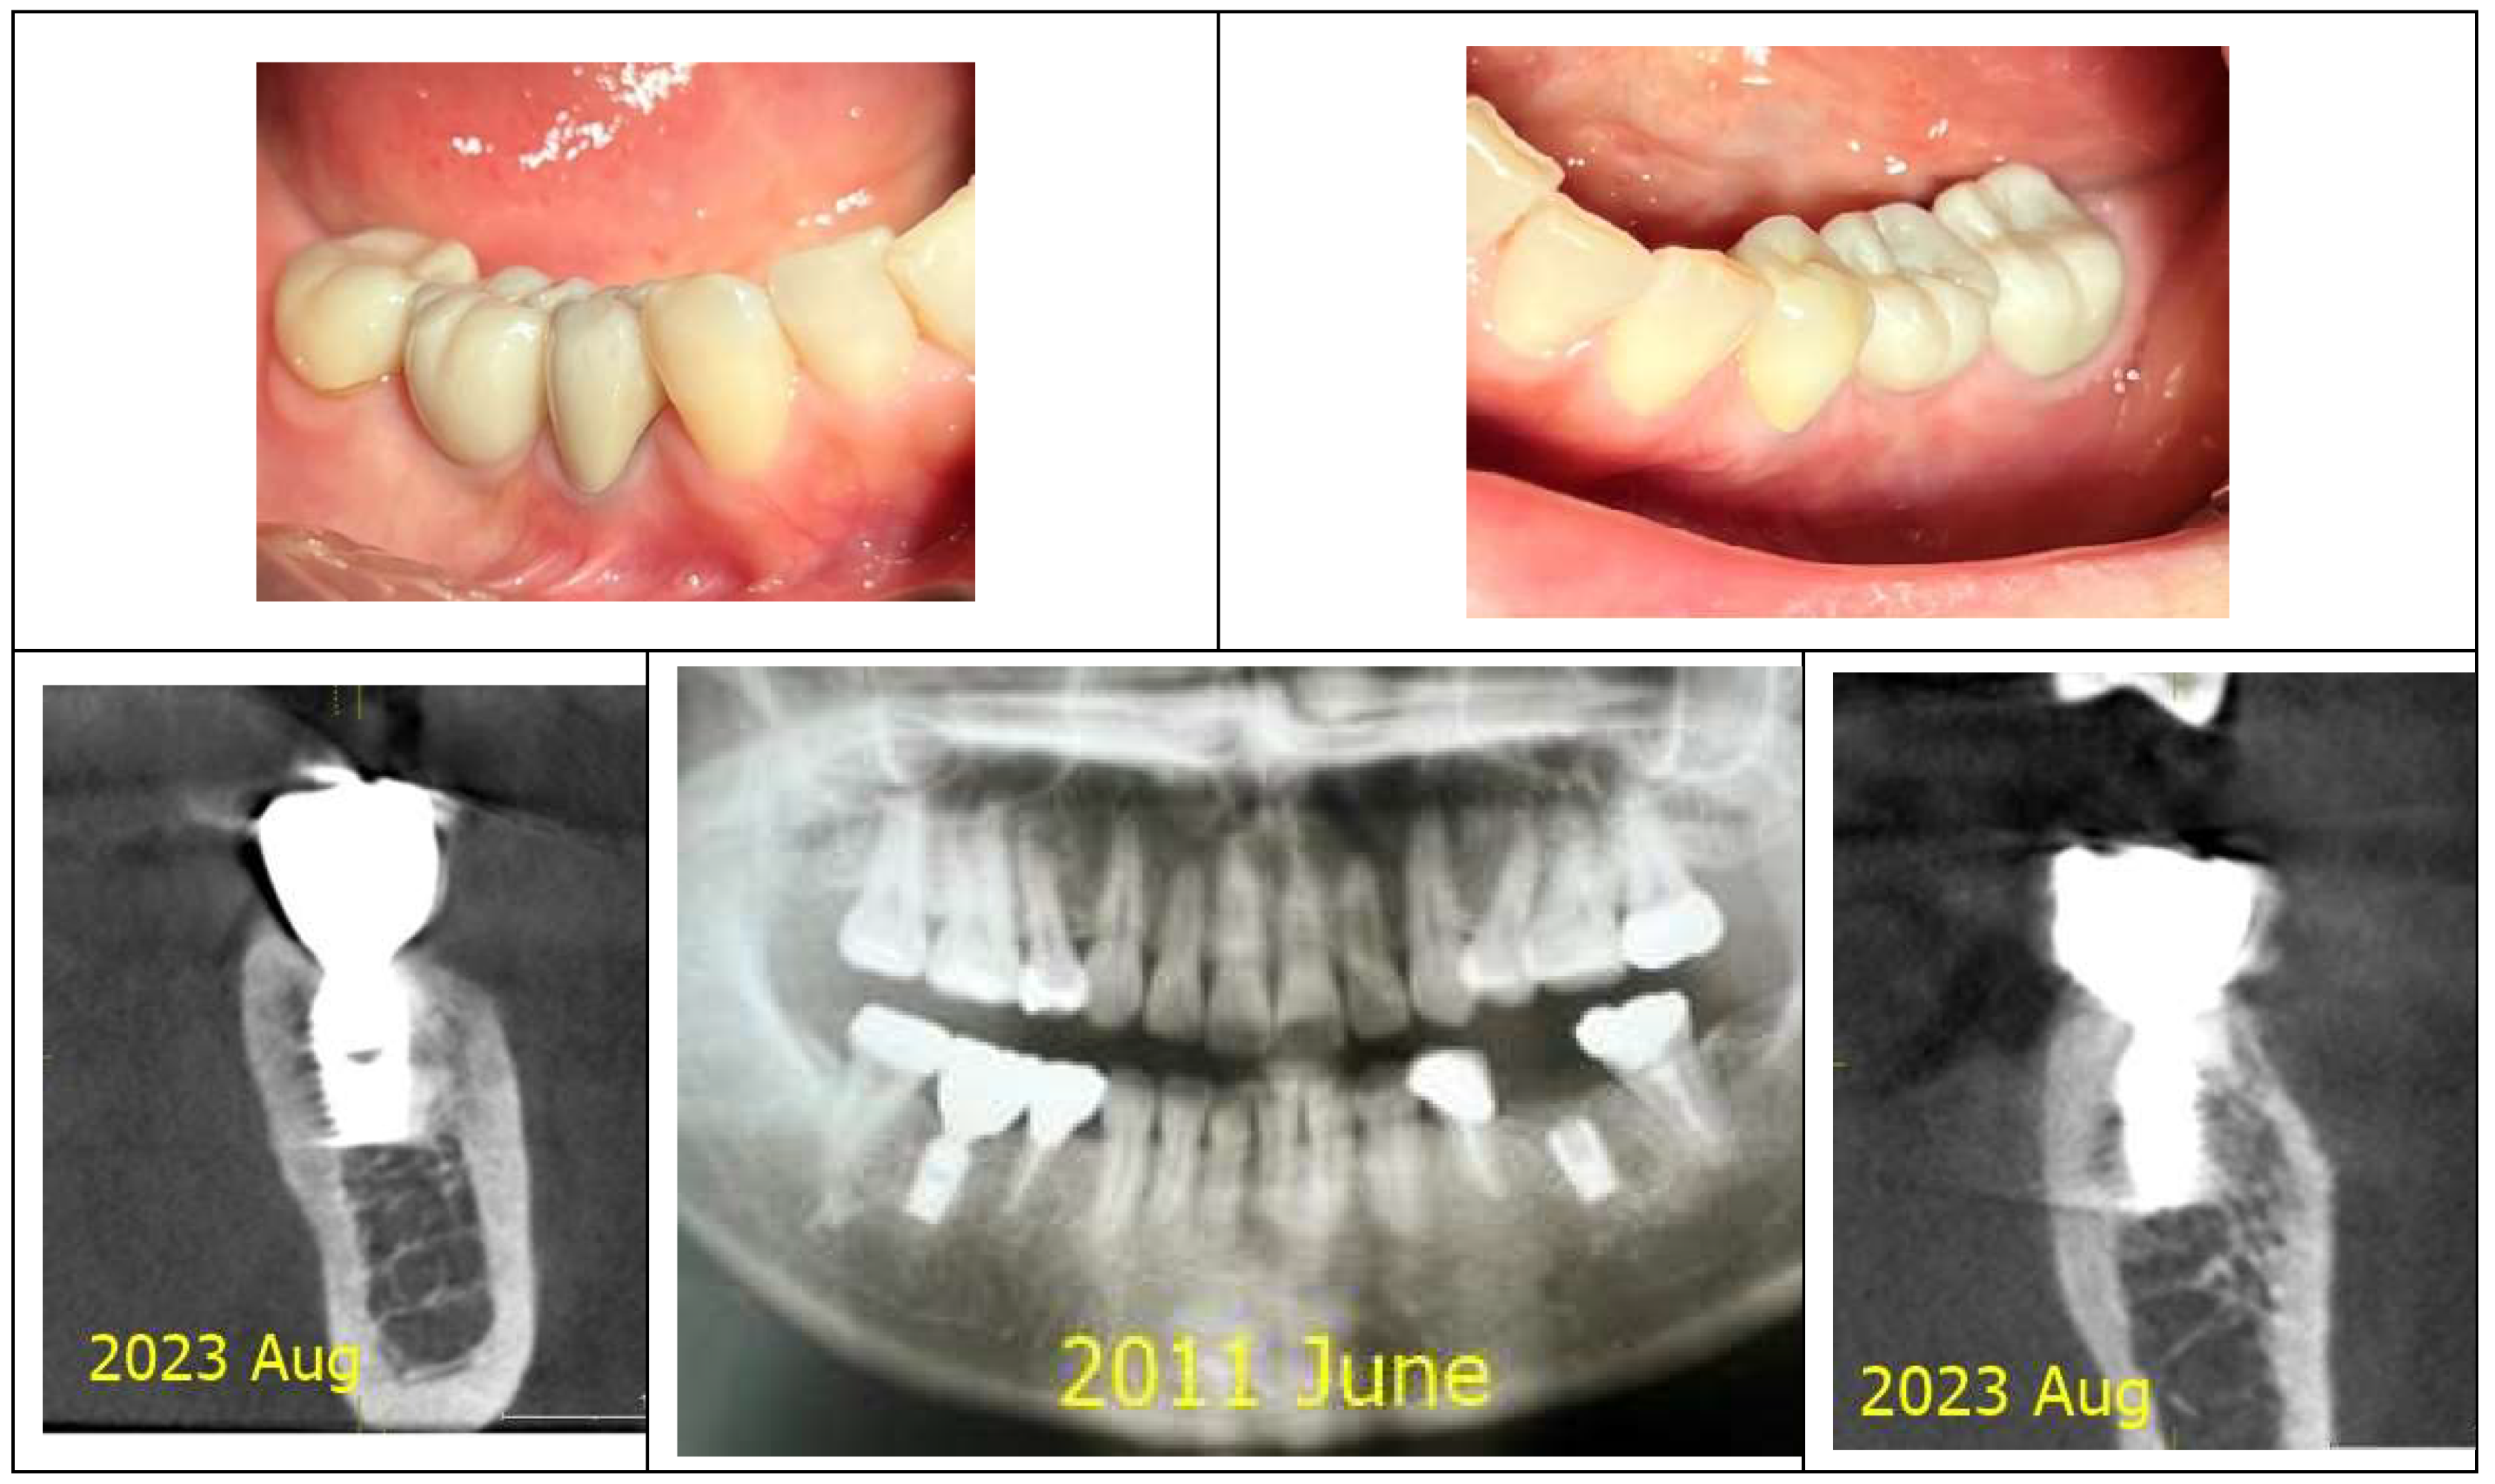

Figure 7 and

Figure 8 illustrate the radiographic changes observed from 2021 to 2024 at the lower right first molar implant site (control site) and the upper left first molar implant site (experimental site), respectively. (

Figure 7,

Figure 8) The clinical photographs taken in 2024 (

Figure 9) depict the final results, showcasing both a stable and natural appearance for both implant sites.

Figure 9.

Clinical images of control and experimental sites post-revision. This figure presents clinical photographs of the control and experimental implant sites following the revision procedure. Both sites exhibit a natural and healthy appearance, indicating successful soft tissue adaptation and restoration aesthetics, taken at 2024.

Figure 10 compares X-rays from October 2021 and July 2024, showing a marked decrease in Crest to Restoration Distance (CRD) after restoration modification. (

Figure 10) The reduction ensured the gap was fully occupied by peri-implant soft tissue, eliminating voids. This suggests that maintaining CRD within a critical range is essential for a stable biological seal, reinforcing the soft tissue barrier against bacterial infiltration.

Figure 10.

Comparison of X-rays taken in October 2021 and July 2024 after the restoration revision, demonstrating a decrease in the CRD. When the CRD is maintained within the critical range, it can be inferred that the gap space is occupied exclusively by peri-implant soft tissue, without voids, and the GRD can be represented as Soft Tissue Thickness (STT).